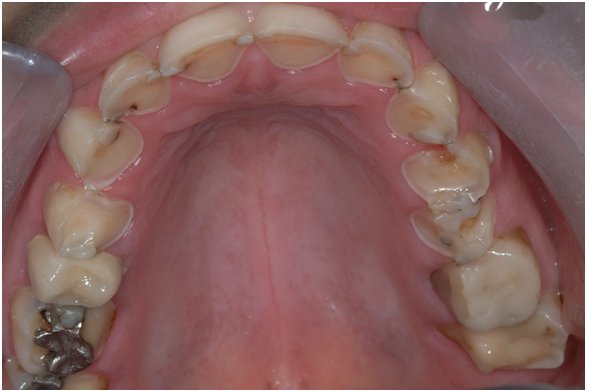

Cáries Dentárias

As cáries dentárias são mais frequentes entre crianças mas os adultos também estão em risco. Os tipos mais comuns de cáries dentárias são:

• Cáries coronárias - o tipo mais comum; ocorre tanto em crianças como em adultos; as cáries coronárias estão localizadas mais frequentemente nas superfícies oclusais ou entre os dentes.

Só o seu dentista pode dizer-lhe com certeza se você tem ou não uma cárie dentária. Isto deve- -se ao facto de as cáries poderem desenvolver-se debaixo da superfície dentária, onde você não consegue ver a olho nu. Quando ingere alimentos que contêm hidratos de carbono (açúcares,etc.), estes hidratos de carbono servem de alimento às bactérias da placa bacteriana que produzem ácidos e penetram no dente. Com o passar do tempo, o esmalte do dente começa a deteriorar-se debaixo da superfíce dentária enquanto esta mantém-se intacta. Quando esta sub- -superfície desaparece, a superfície colapsa expondo a cavidade.

As cáries dentárias desenvolvem-se com mais frequência nas fissuras das superfícies oclusais dos dentes posteriores, entre os dentes e junto à linha gengival. Mas independentemente onde elas ocorram, a melhor forma de detectar e tratá-las antes que se tornem um problema mais sério, é através de uma visita regular ao dentista para consultas de rotina.